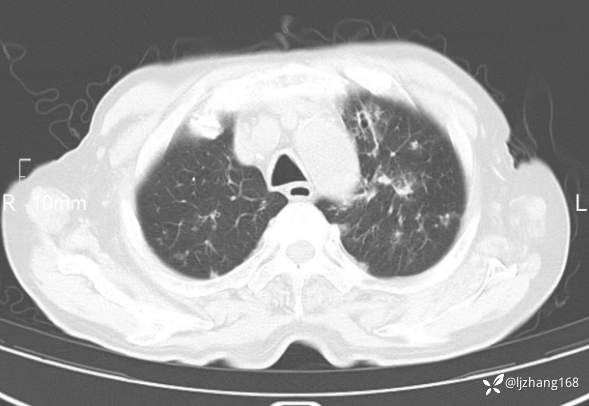

老年男患,咳嗽,气短,双肺多发间质性病变,何种感染?(有结果)

辅助检查:胸部CT:双肺肺气肿,间质性病变,血气分析:PH 7.413, PCO2 29.2mmHg, PO2,81.8mmHg,乳酸 3.3mmol/1,剩余碱-4.0mmol/1,HC03 18.8mmol/1。全血超敏C反应蛋白:超敏C反应蛋白 135.60 mg/L、 白细胞 14x19^9/L,中性粒细胞11.6x10^9/L。